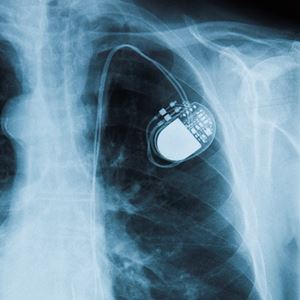

A medical procedure to implant a small electronic device to help regulate your heartbeat.